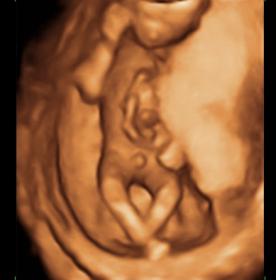

18 Week 3d Ultrasound Gender

Prenatal Peek Myrtle Beach 3d 4d Ultrasound